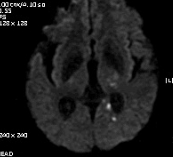

2011-9-10 근력이 G4-  로 지속, 더 이상 나빠지지는 않음. 우측 상지의 움직임이 주과적으로 둔해졌다고 하나 객관적 근력은 정상입니다. Diffusion만 촬영하였습니다.

# 손 o 일 교수님 의견

DWI coronal or saggital view 보면 분명하겠지만 이 사진으로 보니 PCA territory infarction으로 모두 설명되는 것 같습니다. PCA 영역에 hypoperfusion으로 병변이 크지는 것 같습니다. 5-7일 지나야 안정기에 들어갈 것 같습니다.